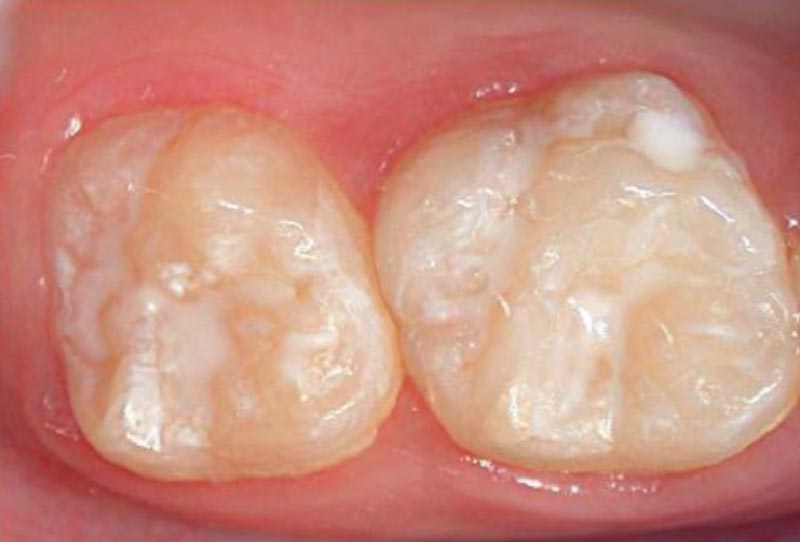

• Fissure sealants1

Fissure sealants BEFORE